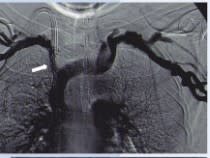

La acumulación casuística después de asistir a más de 20.000 pacientes relacionados con la hemodiálisis (procedimientos en la sala de angiografía, ecografías, mapas vasculares, tratamientos combinados fluoroscopia-ecografía, contrastes alternativos como el CO2, nuevos balones para fístulas - balones cortantes, crioplastia, balón con droga, etcétera), nos animó a plasmar esa experiencia en un libro que pudiera condensar los casos más representativos en la práctica diaria de cualquier radiólogo vascular dedicado al acceso vascular de hemodiálisis. De esta forma, hemos hecho un esfuerzo por imaginarnos a nuestros colegas en su día a día enfrentándose a este campo tan apasionante del vascular intervencionismo. Para ello, hemos planteado este libro con un formato que ayude al especialista a entender cómo tiene que enfocar cada caso desde las esquinas de la clínica, la técnica y el protocolo de actuación; es decir, tal como nosotros mismos venimos haciéndolo diariamente.

Cada caso viene presentado como si fuese una historia clínica, con su motivo de consulta y sus antecedentes personales, especialmente los referidos a los accesos vasculares de hemodiálisis, seguido de una exploración física. Se acompaña de un informe del procedimiento realizado con la técnica empleada y los abordajes, así como los balones de angioplastia y/o stents utilizados. Para finalizar, escribimos unos comentarios sobre el procedimiento realizado y todo caso va acompañado de un gran número de imágenes explicativas de alta calidad